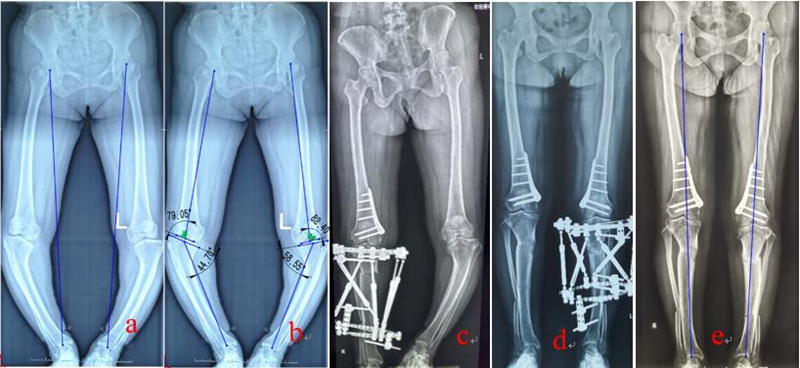

王学等[27]利用国内自主研发的数字六轴外架(QSF)治疗膝关节复杂畸形,钟豪良等[28]利用QSF治疗成人Blount 病,均取得良好疗效。该数字六轴外架配套软件基于CT数据,亦是目前国际上唯一的基于CT数据的配套软件,所以复位精度更高,而且其复位精度不受外固定架的安装位置、X线放大率、拍摄角度等的影响。所以与国际上的其它六轴外架产品比较,具有复位精度高,操作简便、学习曲线短等优点。临床使用时,医生不需要测量骨折或畸形的6个移位参数,以及环的4个安装参数,后台工程师根据CT数据计算6根连接杆的调节数据,医生根据该数据,将各连接杆的长度调节到位即可。优点是复位精度高,对外固定架的安装无特殊要求,操作更简便,降低医生的学习曲线,同时大大简化了临床医生的繁琐工作,也不需要医生学习掌握软件操作。但由于不是医生自己测量和软件运算,所以不能实时获得处方。

图3:QSF结合内固定治疗双侧Blount病 a:术前双下肢力线;b:畸形分析:股骨外翻,胫骨内翻、内旋、短缩;c、右侧股骨远端闭合截骨即时矫正内固定、六轴外架缓慢矫正胫骨畸形;d:左侧股骨远端内侧闭合截骨即时矫正内固定、六轴外架缓慢矫正胫骨畸形;e:双侧矫形术后,力线恢复良好,内旋纠正,双下肢等长。